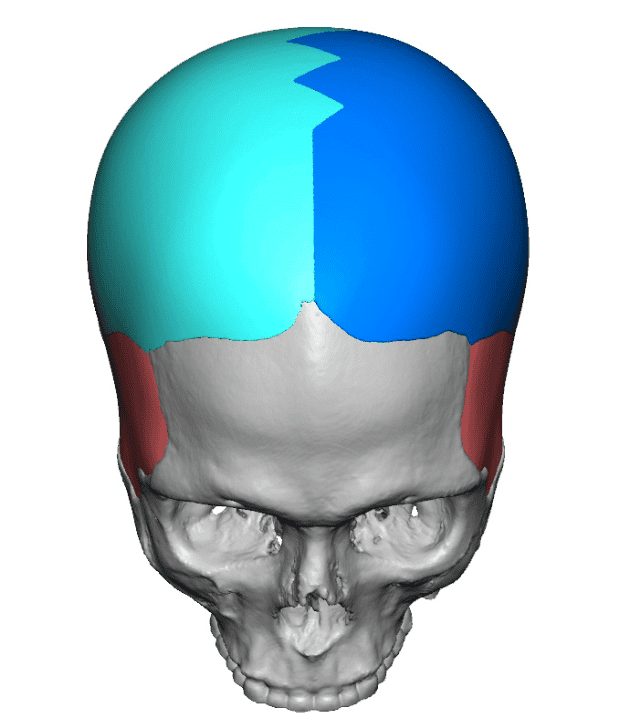

Desire for major head reshaping with a taler and wider head shape.

Placement of large two piece custom skull implant through a sagittal scalp incision.